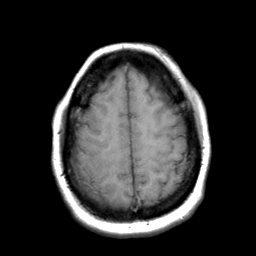

Cerebral hemorrhage, MR Study mr-t1 -- Slice #19

[Home][Help][Clinical] Slice 19